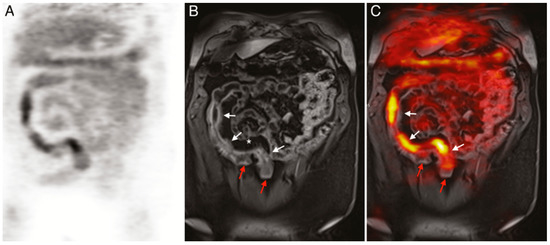

PET imaging is currently the only clinically approved molecular imaging approach for GI inflammation [95][96]. Specifically, 18F-FDG PET is used to measure the extent and magnitude of GI inflammation, indicating areas of low or high inflammation based on metabolic differences throughout the GI tract. The high metabolic need of inflamed tissue alongside the increased presence and activity of immune cells, such as leukocytes, results in increased glucose metabolism at sites of inflammation [126]. Differences in 18F-FDG consumption highlight areas of increased inflammation while contrasting against normal healthy tissue. PET alone offers limited spatial resolution despite its potential for high contrast imaging. Additionally, the uptake of 18F-FDG occurs in off-target sites, resulting in high background signal. As such, PET is frequently paired with either CT or MRI imaging to better monitor disease status and accurately assess disease location, as shown in (Figure 5) [127][128][129].

Figure 5. (A) 18F-FDG PET image of human patient with Crohn’s disease. (B) T1-weighted magnetic resonance imaging (MRI) image of the same patient. (C) Merged PET/MRI. White arrows indicate locations of acute inflammation while red arrows highlight damage resulting from earlier disease action. The asterisk (*) shows a site of proliferation of fibrofatty compounds in the mesentery. SUVmax of 18F-FDG 5.6–9.2 vs. SUVmax of background bowel 1.5–2.8 [128].